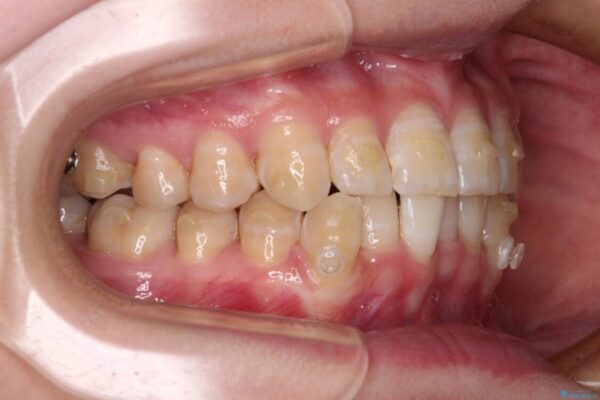

治療途中

• 【モニター】下顎前歯のデコボコをインビザラインできれいに 治療途中画像